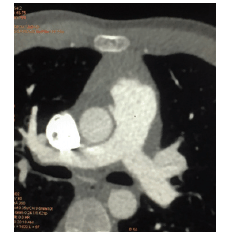

A origem anômala das artérias coronarianas é uma entidade relativamente rara, podendo se apresentar de várias formas clínicas e evoluir de forma adversa. A angiotomografia multislice das artérias coronarianas vem ganhando espaço na prática clínica diária, representando importante método propedêutico, com grande potencial na avaliação anatômica dessas artérias. Considere a seguinte imagem:

A anomalia coronária detectada na imagem é: